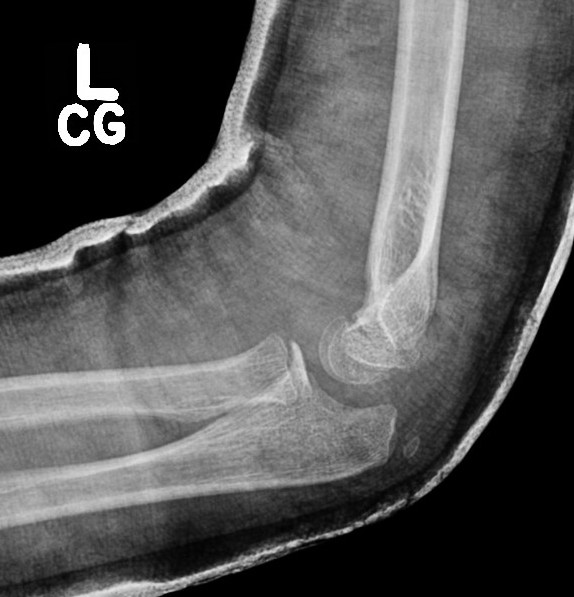

Case 1. Missed Monteggia, injury 6 months ago